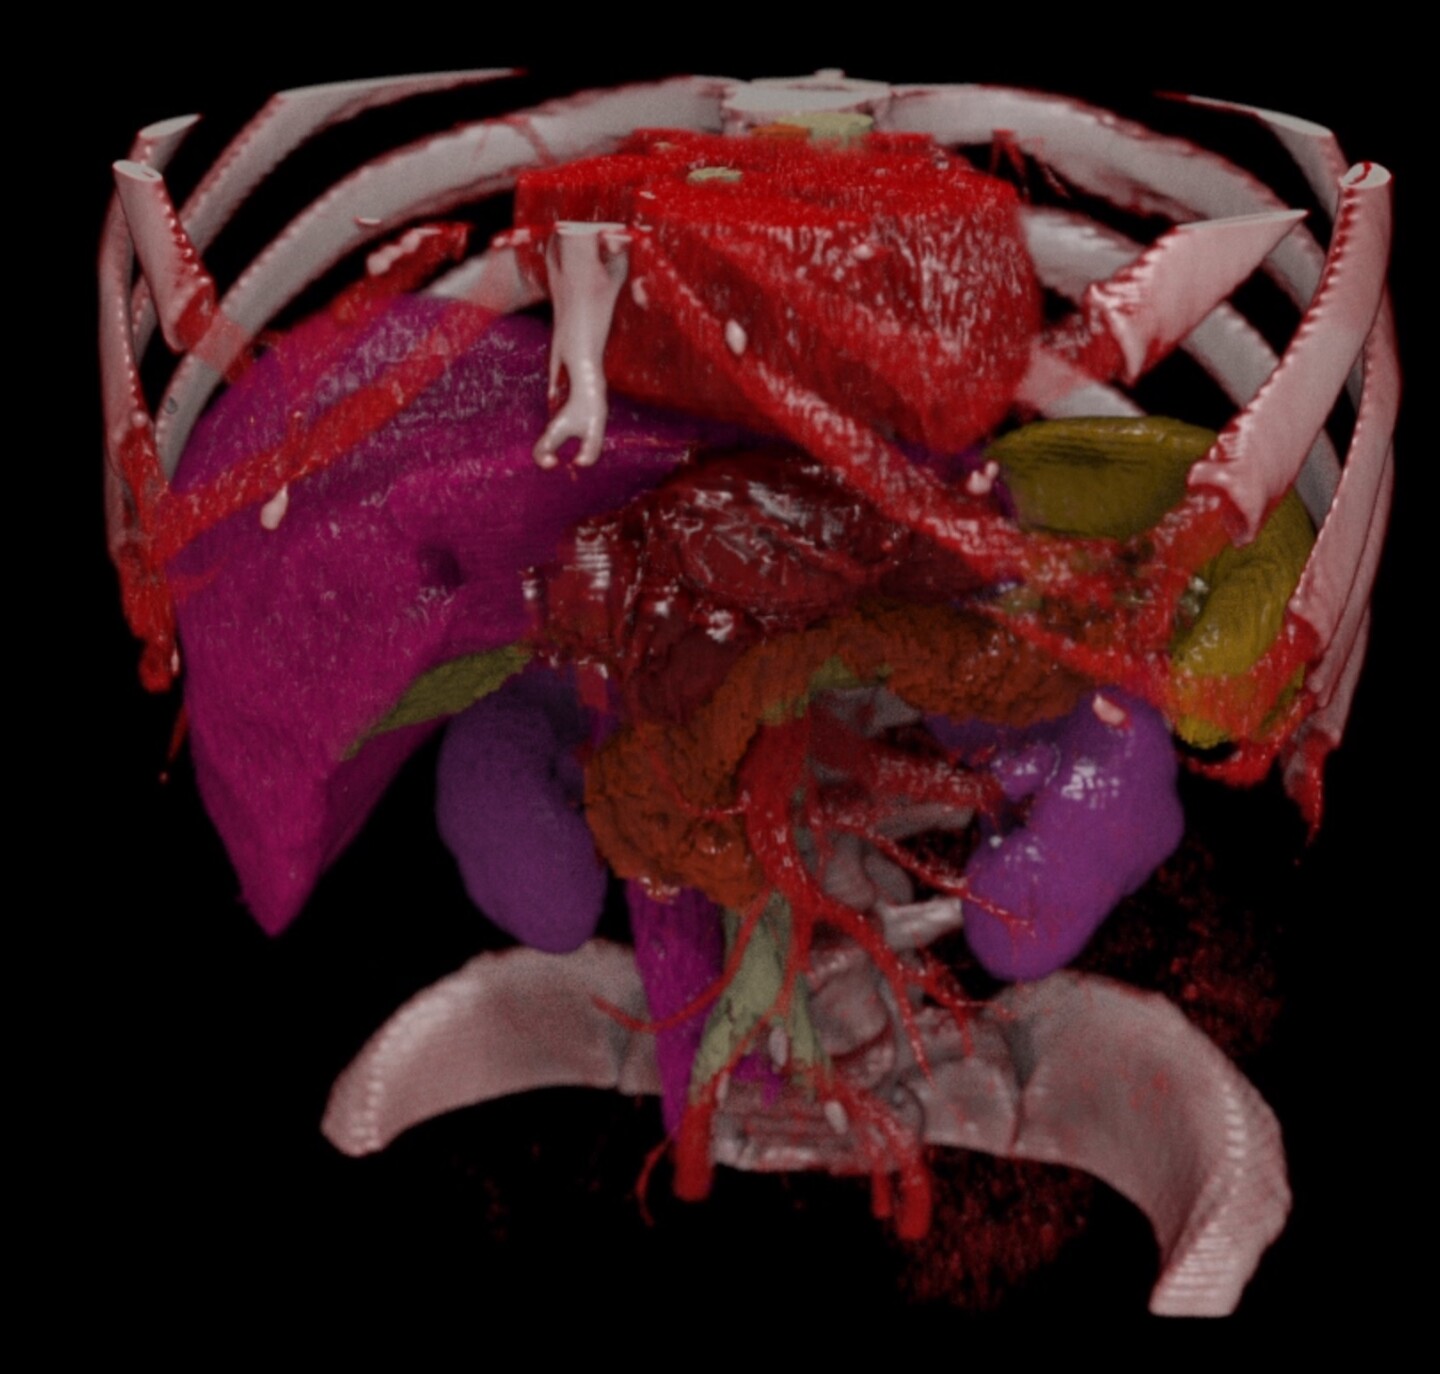

The toolkit includes a base container with MONAI Core, MONAI Label, and NVIDIA FLARE. It also features a curated library of 15 pre-trained models covering a wide range of medical imaging modalities including CT, MR, Pathology, and Endoscopy. Available on NGC, this toolkit empowers data scientists and clinical researchers to accelerate their AI development in medical imaging.